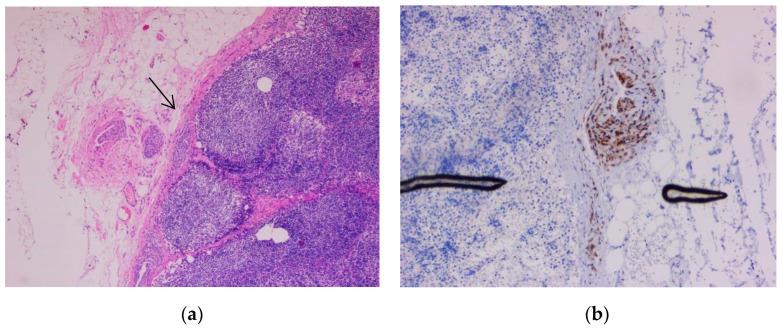

We present 100 melanoma cases and one capsular nevus case. The most common type was nodular melanoma. The immunohistochemistry markers used were SRY-box transcription factor 10 (SOX10), S100 protein, human melanoma black 45 (HMB45), and melanoma antigen recognized by T cells 1 (Melan-A). Uveal melanoma and conjunctival melanoma represent particular tumors with independent prognostic factors. Uveal melanoma requires assessment of macrophages, microvascularisation, and mitoses. Sentinel lymph node metastases are essential targets that provide staging tools. Conjunctival melanoma and capsular nevi are diagnostic pitfalls.

Melanoma can appear in various forms, and sometimes the diagnosis might be unclear. Today, immunohistochemistry remains the most important tool in confirming the diagnosis and prognosis for this type of neoplasia.